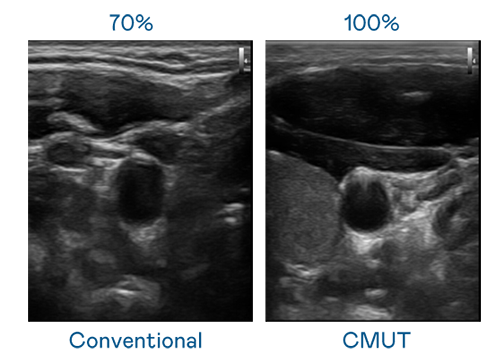

CMUT 技术是一种用电容式微机电元件来产生超音波讯号的技术。与传统 PZT 压电式技术相比,CMUT 频宽增加 30%,更宽频的超音波讯号让影像解析度大幅提升,是实现高影像品质医疗超音波扫描、促进精准医疗发展的关键技术。

大频宽带来超清晰影像

超音波影像的解析度高低,首先取决于探头能发出的讯号频宽。大米星球官网入口 CMUT 可提供高清晰的超音波讯号,提供高频宽、高灵敏度、影像纹理细节更高的超音波影像,协助医护人员缩短影像判读时间及利用精准的医疗影像进行诊断。